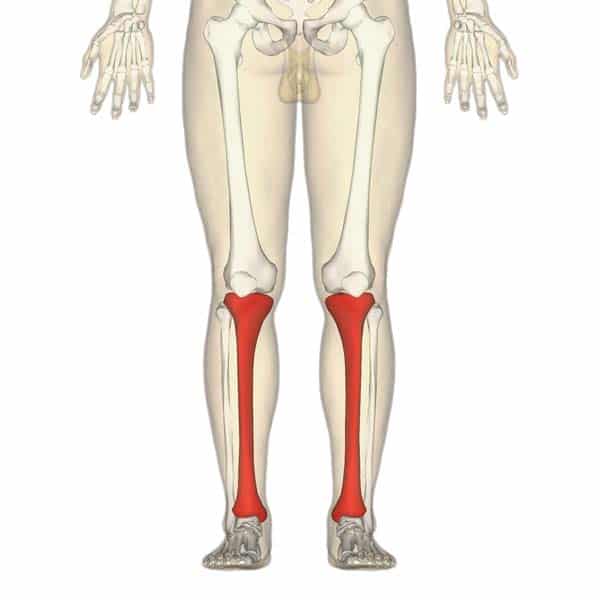

The tibia is the main bone of the lower leg, forming what is more commonly known as the shin. It expands at its proximal and distal ends; articulating at the knee and ankle joints respectively. The tibia is the second largest bone in the body and it is a key weight-bearing structure. In this article, we shall look at anatomy of the tibia – its bony landmarks, articulations and clinical correlations. By Anatomography [CC-BY-SA-2.1-jp], via Wikimedia Commons Fig 1Overview of the tibia in the human skeleton Pro Feature - 3D Model You've Discovered a Pro Feature Access our 3D Model Library Explore, cut, dissect, annotate and manipulate our 3D models to visualise anatomy in a dynamic, interactive way. Learn More Proximal The proximal tibia is widened by the medial and lateral condyles, which aid in weight-bearing. The condyles form a flat surface, known as the tibial plateau. This structure articulates with the femoral condyles to form the key articulation of the knee joint. Located between the condyles is a region called the intercondylar eminence – this projects upwards on either side as the medial and lateral intercondylar tubercles. This area is the main site of attachment for the ligaments and the menisci of the knee joint. The intercondylar tubercles of the tibia articulate with the intercondylar fossa of the femur. By TeachMeSeries Ltd (2025) Fig 2The tibial plateau. The tibial condyles articulate with the femoral condyles to form the knee joint. Shaft The shaft of the tibia is prism-shaped, with three borders and three surfaces; anterior, posterior and lateral. For brevity, only the anatomically and clinically important borders/surfaces are mentioned here. Anterior border – palpable subcutaneously down the anterior surface of the leg as the shin. The proximal aspect of the anterior border is marked by the tibial tuberosity; the attachment site for the patella ligament. Posterior surface – marked by a ridge of bone known as soleal line. This line is the site of origin for part of the soleus muscle, and extends inferomedially, eventually blending with the medial border of the tibia. There is usually a nutrient artery proximal to the soleal line. Lateral border – also known as the interosseous border. It gives attachment to the interosseous membrane that binds the tibia and the fibula together. By TeachMeSeries Ltd (2025) Fig 3Bony landmarks of the tibial shaft. Clinical Relevance Intraosseous Access Intraosseous access is a form of vascular access used in the emergency setting. It allows the administration of fluids, blood products and medications directly into the bone marrow. IO access is typically used in an emergency when intravenous access is not obtainable. There are two main sites in the tibia that are suitable for IO access: Anteromedial surface, 2-3cm below the tibial tuberosity Proximal to the medial malleolus Complications of IO access include osteomyelitis, iatrogenic fracture and compartment syndrome. IO infusions should be discontinued when IV access has been achieved. Distal The distal end of the tibia widens to assist with weight-bearing. The medial malleolus is a bony projection continuing inferiorly on the medial aspect of the tibia. It articulates with the tarsal bones to form part of the ankle joint. On the posterior surface of the tibia, there is a groove through which the tendon of tibialis posterior passes. Laterally is the fibular notch, where the fibula is bound to the tibia – forming the distal tibiofibular joint. Clinical Relevance Fractures of the Tibia Fractures of the tibia are relatively common. There are two main types: High energy trauma – occurs predominantly in the younger population. Low energy trauma or insufficiency fractures – occurs predominantly in the elderly. Fractures most commonly occur at the shaft of the tibia, and are typically associated with fibula fractures. Fractures of the proximal tibia are known as tibial plateau fractures; the condyles may be broken and injury to the menisci and ligaments of the knee is not uncommon. These fractures are classified using the Schatzker classification, and if very displaced will likely required operative management. It is important to monitor patients for signs of compartment syndrome in the pre-and post-operative phases. At the ankle, the medial malleolus can be fractured. This is caused by the ankle being twisted inwards (over-inversion) – the talus of the foot is forced against the medial malleolus, causing a spiral fracture. This rarely happens in isolation and typically the lateral malleolus is also fractured; potentially producing an unstable fracture that requires operative management. By James Heilman, MD [CC-BY-SA-3.0], via Wikimedia Commons Fig 4Fracture of the medial malleolus (black arrow) in a child, with the whiting arrow marking a normal growth plate. This is a Salter Harris type III fracture. Do you think you’re ready? Take the quiz below Pro Feature - Quiz The Tibia Question 1 of 3 Submitting... Skip Next Rate question: You scored 0% Skipped: 0/3 1800 More Questions Available Upgrade to TeachMeAnatomy Pro Challenge yourself with over 1800 multiple-choice questions to reinforce learning Learn More Rate This Article